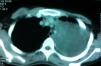

Caso clínicoPaciente de 19 años de edad que fue ingresada en nuestro hospital refiriendo dolor en el brazo izquierdo. No presentaba otros síntomas. Tanto la exploración física como la anamnesis fueron anodinas. Se obtuvo una radiografía de tórax simple, que reveló una extensa opacidad que abarcaba casi todo el hemitórax izquierdo y causaba una desviación de la tráquea y el mediastino a la derecha (fig. 1). Acto seguido, para definir mejor esta lesión, efectuamos una exploración mediante tomografía computarizada (TC), que reveló una masa heterogénea y sólida de 16×15×15cm (fig. 2). La masa se extendía hasta la región supraclavicular izquierda sin destrucción ósea. Se caracterizaba por contornos lisos y demostraba una relación directa con las estructuras vasculares mediastínicas sin obliterarlas. El pulmón izquierdo estaba colapsado por completo. Después de la TC, la paciente se sometió a una resonancia magnética (RM) para una evaluación más detallada. La masa se originaba a partir del mediastino posterior, donde manifestaba una baja intensidad de señal en T1 y una alta intensidad de señal, heterogénea en las imágenes RM ponderadas en T2, y, tras la administración de gadolinio (0,1mmol/kg), se demostró un intenso realce del contraste. Consideramos la posibilidad de un linfoma o, menos probable, de un carcinoma pulmonar primario como diagnóstico inicial, por lo que también efectuamos una tomografía de emisión de positrones (TEP-TC) que reveló un aumento de la captación de fluorodesoxiglucosa (18FFDG) por la masa. Para un diagnóstico definitivo, se efectuó una biopsia con aguja transtorácica, guiada con TC. El examen histopatológico reveló capas de células redondas, azules, de pequeño tamaño y con núcleos redondos de pequeño tamaño, y un citoplasma escaso. El análisis inmunohistoquímico demostró una tinción positiva para CD99 y vimentina. Fue negativo para todos los marcadores de linfoma, incluido CD31, CD34, CD45, desmina y citoqueratinas. En función de estos hallazgos, la masa se diagnosticó como un SEE. Acto seguido, se consultó con el servicio de cirugía torácica y se programó una intervención para la exéresis de la lesión.